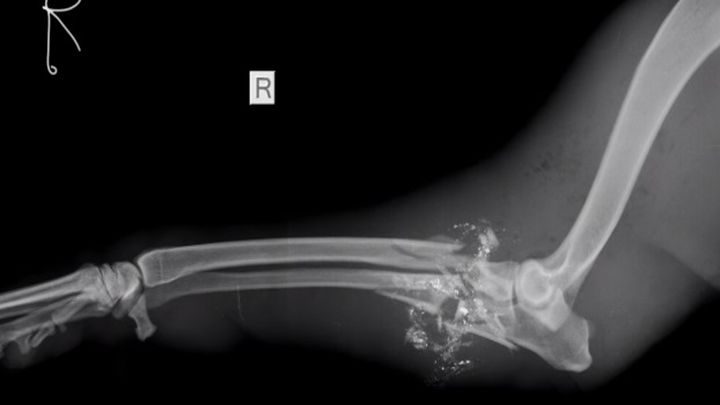

Пуля размозжила Майре лапу, но дети были спасены

Её передали в клинику общества помощи животным The Cape of Good Hope SPCA. К сожалению врачам пришлось ампутировать переднюю лапу отважной защитницы, но собака осталась жива.